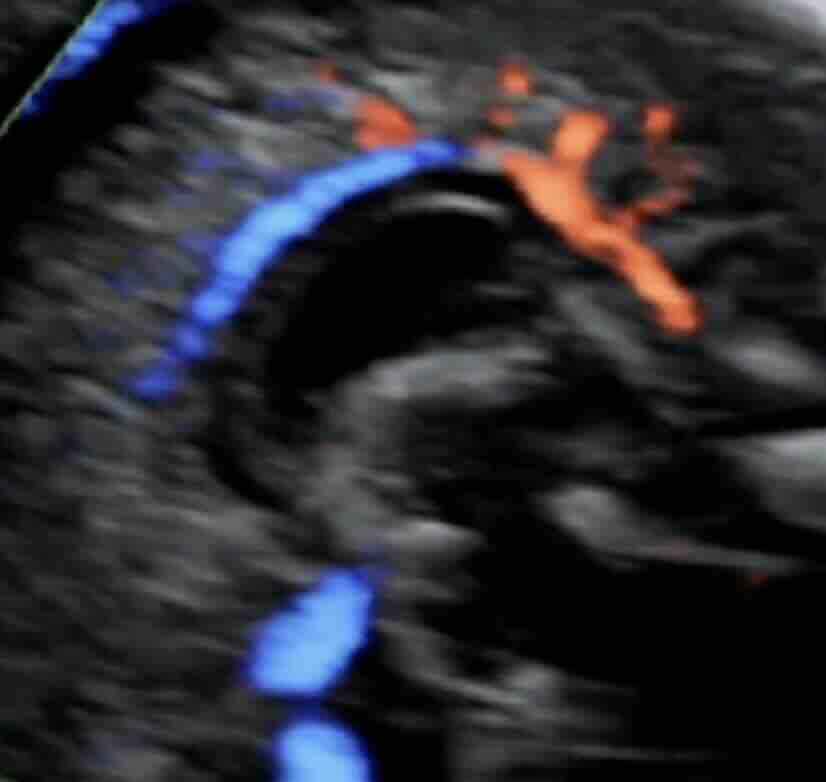

Rahim filmi, rahim iç boşluğunu ve tüplerin açıklığını değerlendirmek için yapılan özel bir röntgen görüntüleme yöntemidir.

Bu işlem sırasında rahim içine kontrast madde verilir ve röntgen altında görüntü alınır. Eğer tüpler açıksa kontrast tüplerden karın içine yayılır. Eğer tıkanıklık varsa kontrast ilerlemez ve bu durum net şekilde görülür.